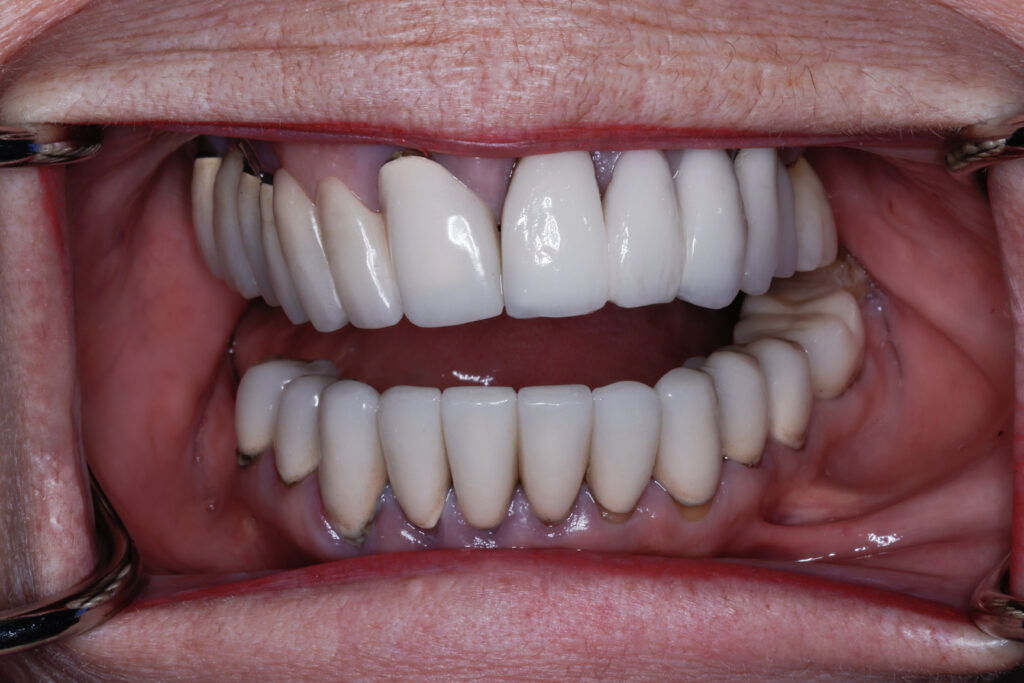

Before

After